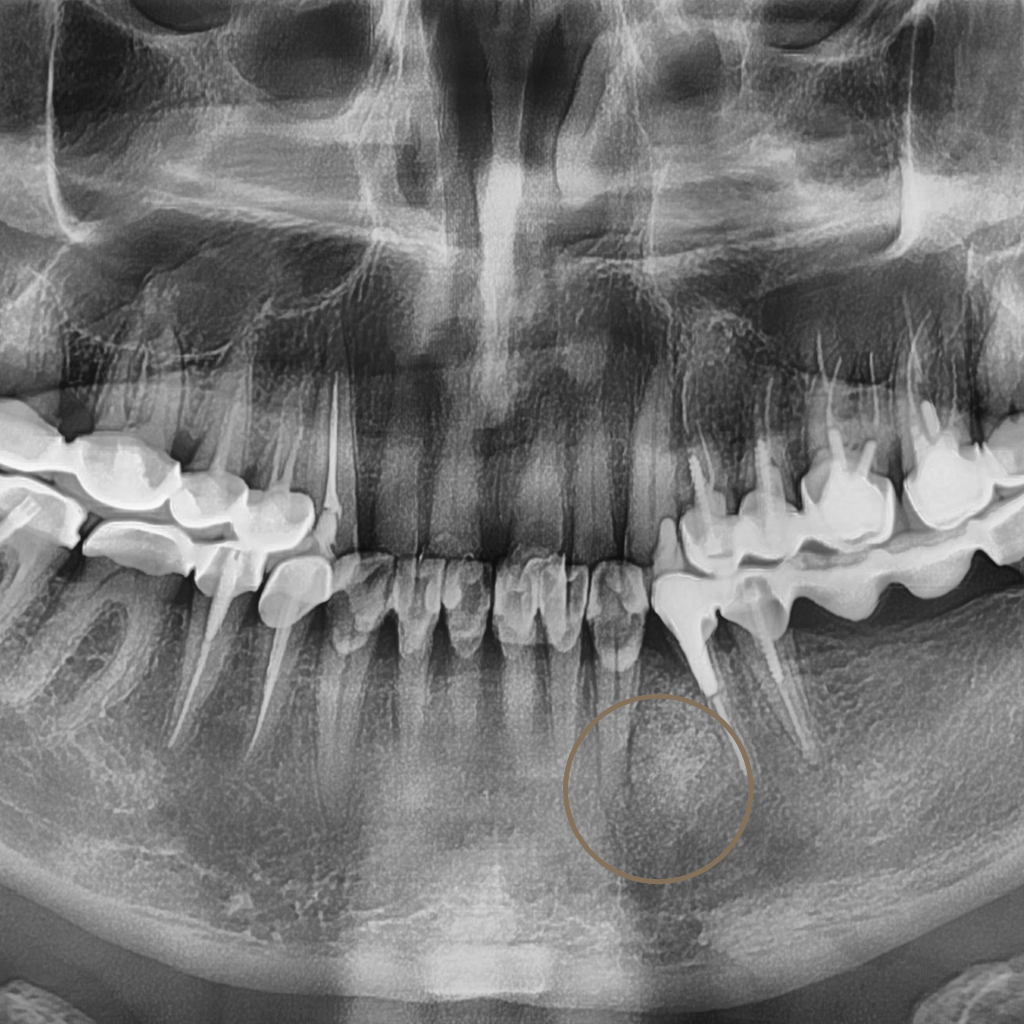

Зъб, който не е пробил напълно или е останал задържан в костта, се нарича ретиниран. Най-често това засяга мъдреците, но може да се отнася и за други зъби. В много случаи състоянието протича без симптоми, но може да доведе до болка, възпаление или увреждане на съседни зъби.

Когато ретинираният зъб създава или крие риск от възпаление, болка, увреждане на съседни зъби или затруднява хигиената в зоната, хирургичната намеса е препоръчителна. Най-често това се отнася за мъдреците, но ретенция може да се наблюдава и при други зъби, като кучешки или премолари.

В някои случаи ретинираният зъб може да остане безсимптомен за дълъг период. В Aesthetico решението за хирургична екстракция се взема индивидуално, след внимателна оценка на позицията на зъба и потенциалните рискове, включително при по-сложни анатомични ситуации.